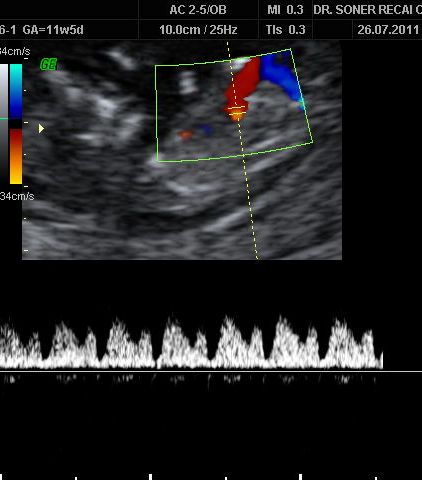

Kalp odacıklarındaki kan akımlarının incelenmesi ve kalpteki delikleri tesbit etmemize yarayan Doppler incelemesi